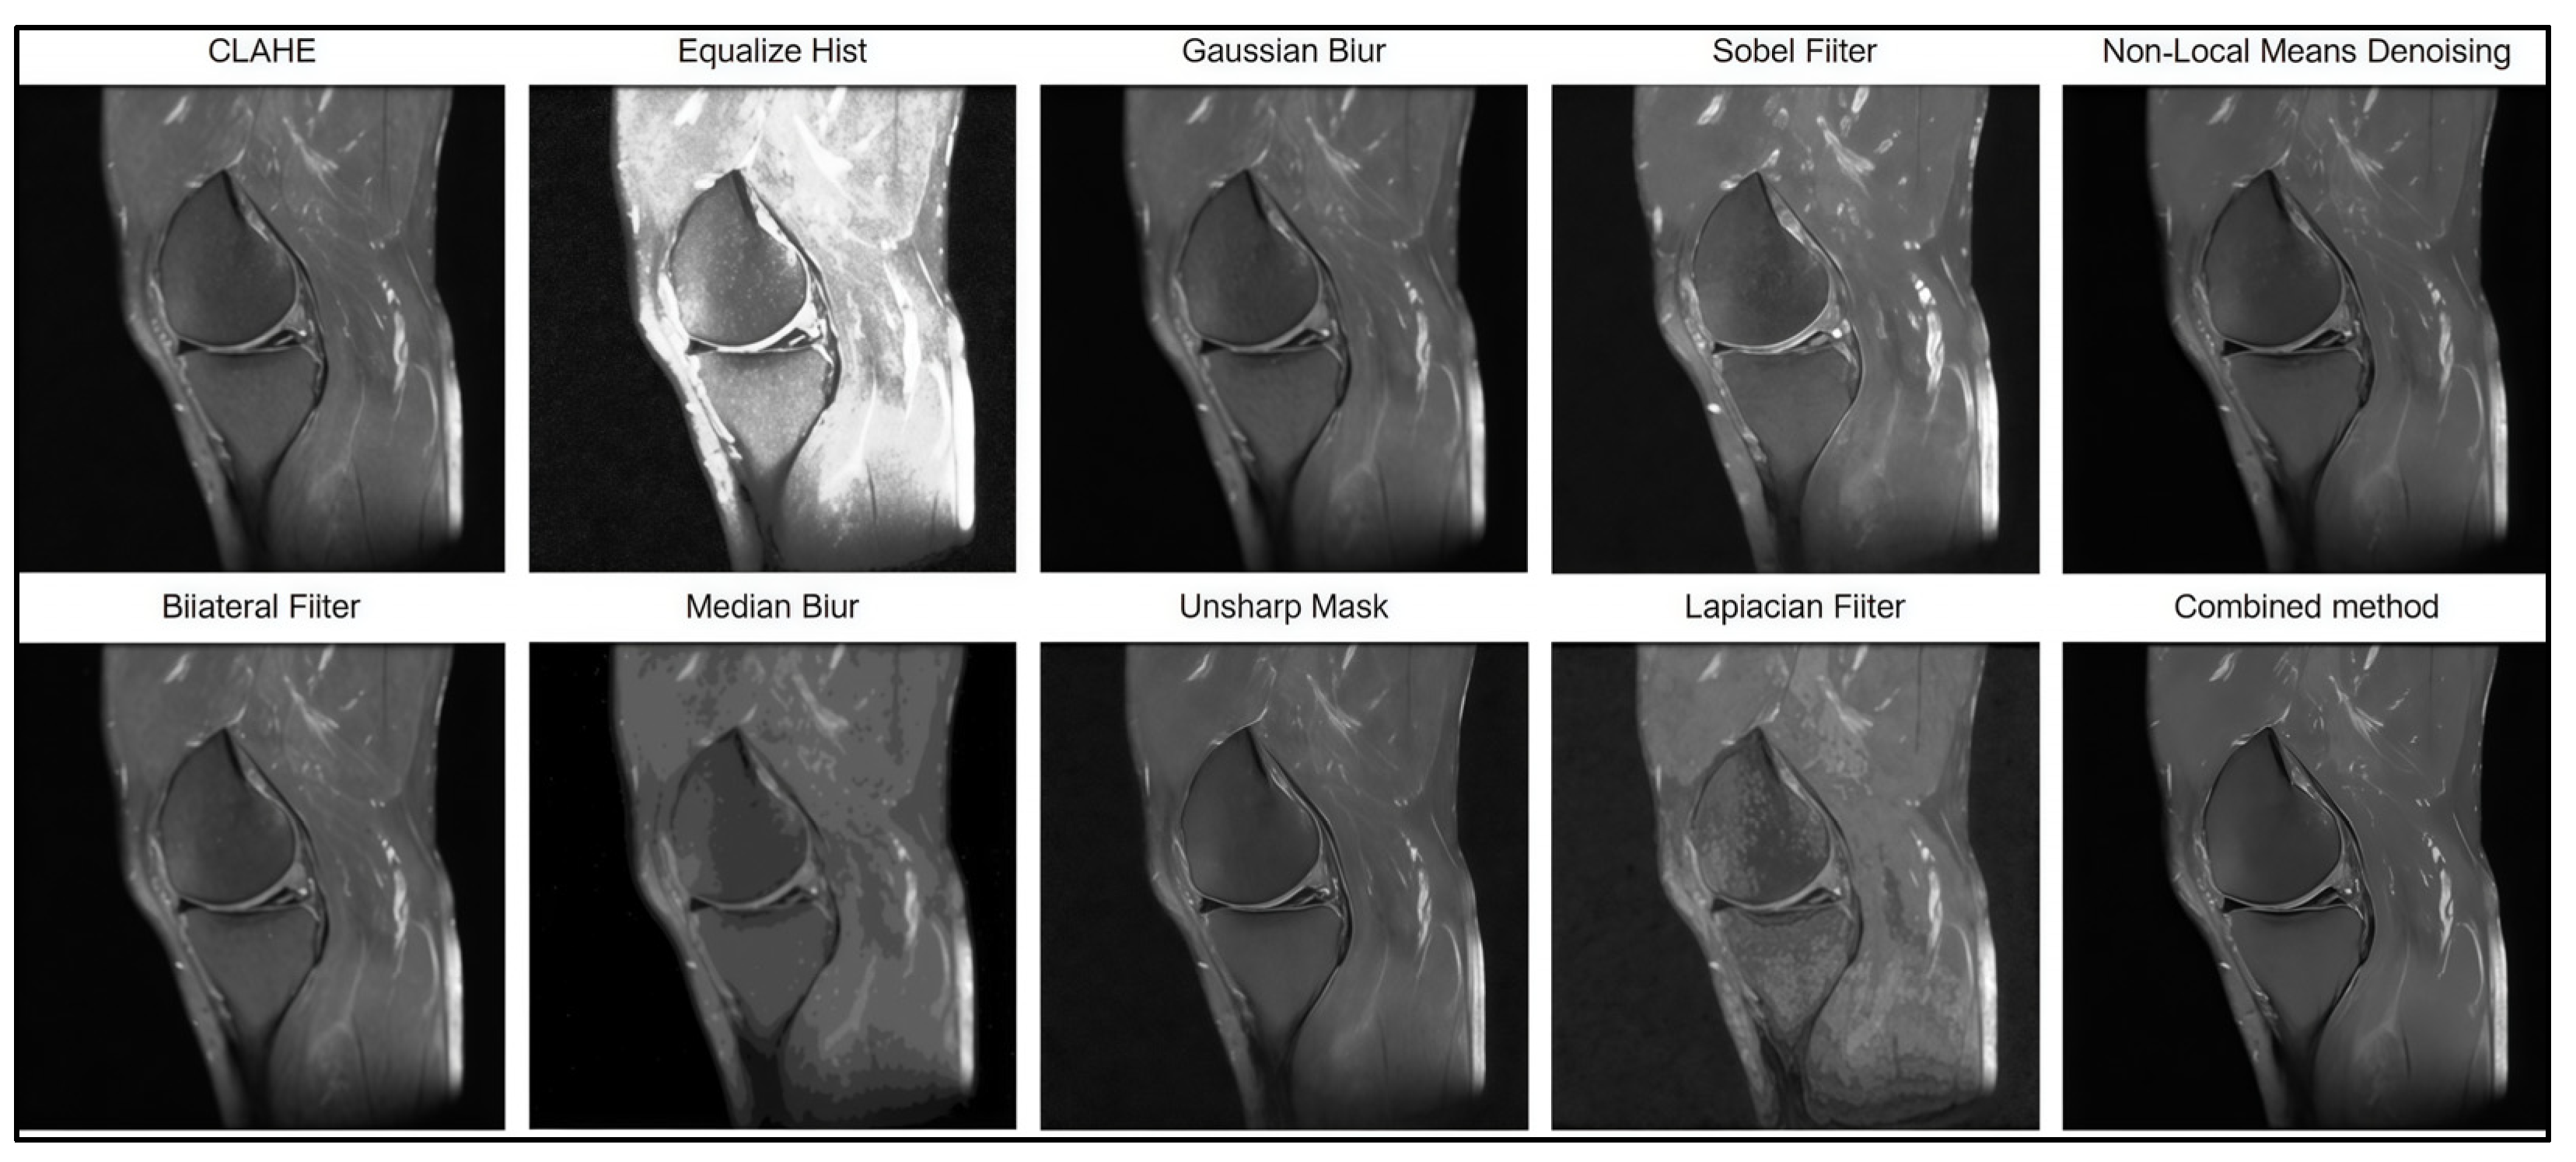

The filter preprocessing stages, which are shown in Figure 3, involved the investigation and testing of contrast enhancement (CLAHE, Equalize Hist), noise reduction (Gaussian Blur, Median Blur, Bilateral Filter, Non-Local Means Denoising), and sharpening (Unsharp Mask, Laplacian Filter, Sobel Filter) techniques. The metrics of MSE (mean square error), pSNR (peak signal-to-noise ratio), and SSIM (structural similarity) were used for performance evaluation.

Figure 3.

Stages of filter preprocessing of images.

For a visual assessment of the effectiveness of each filter, Figure 4 presents the image preprocessing results obtained using the tested algorithms. The displayed MRI image fragments allow a visual comparison of the degree of noise suppression and the preservation of anatomical details for each method.

Figure 4.

Results of image processing using various methods.

A quantitative assessment of effectiveness is presented in Table 3, which reports the values of the MSE, PSNR, and SSIM metrics.

Based on the results of the comparative analysis, the combined approach of Non-Local Means Denoising and Unsharp Mask was selected, as it demonstrated the best quantitative performance (MSE = 32.55; PSNR = 41.37; SSIM = 0.92), indicating its high effectiveness in MRI image preprocessing. In addition, this method produced the most visually satisfactory results, achieving optimal noise suppression while preserving anatomical boundaries (Figure 5).